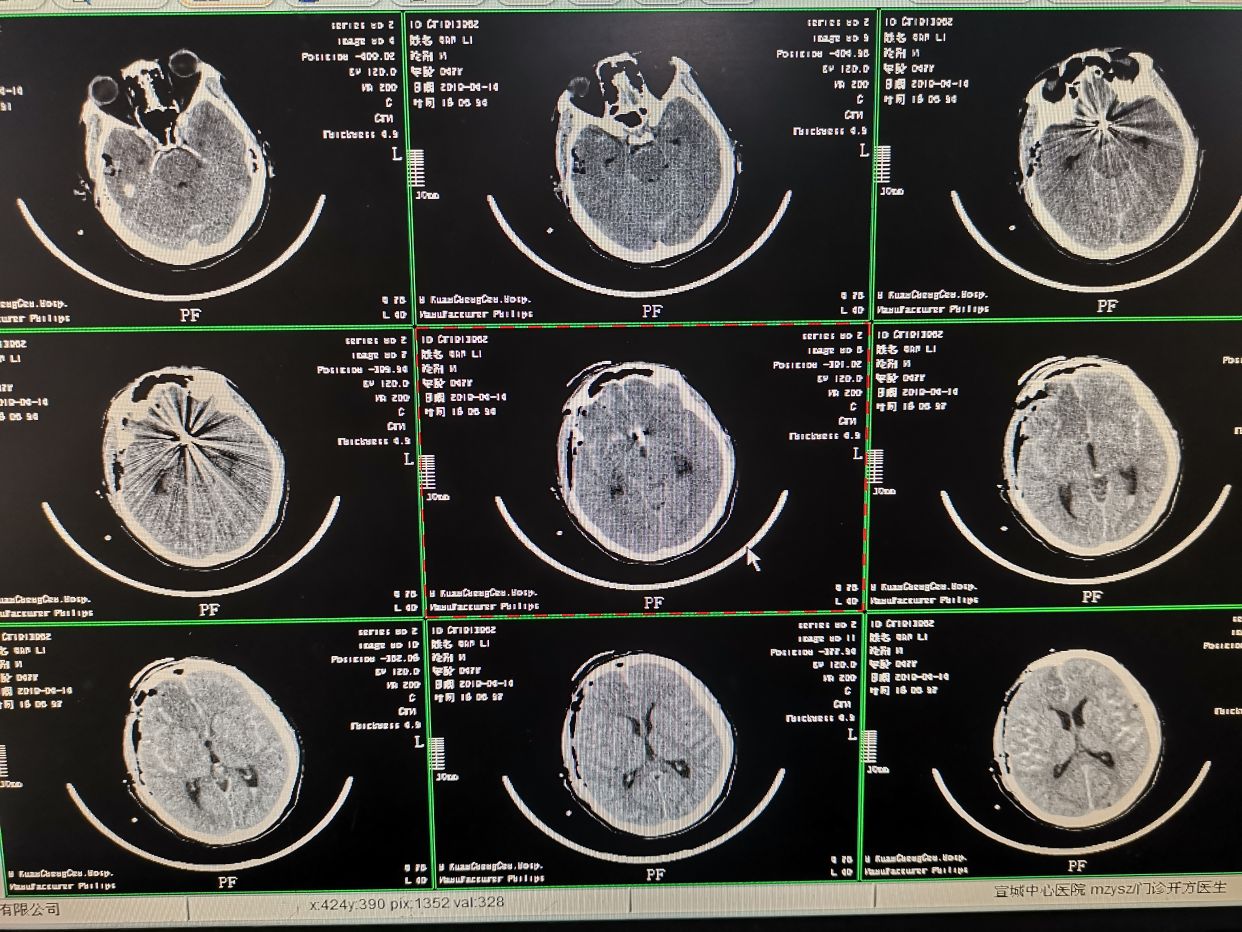

术后即刻CT。术后给予对症支持治疗。

术后第八天CT